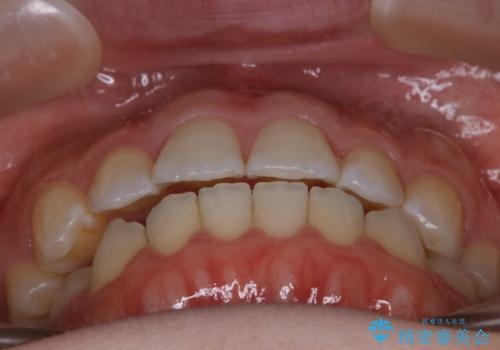

【非抜歯】上下の前歯が噛み合わないオープンバイトの治療

奥歯を沈めて噛み込みを深くしていくことで被害の改善が起こるとともに、下顎自体が前上方に回転移動することで顔貌的にも変化を出すことができます。

前者の場合は臼歯を圧下し沈めてあげることで改善させます。後者の場合は前方に傾斜している歯を元の角度に戻してあげることで改善しますが、舌癖がある場合はその癖自体を無くす治療をしない限りまた同じ状態へと後戻りしてしまいます。